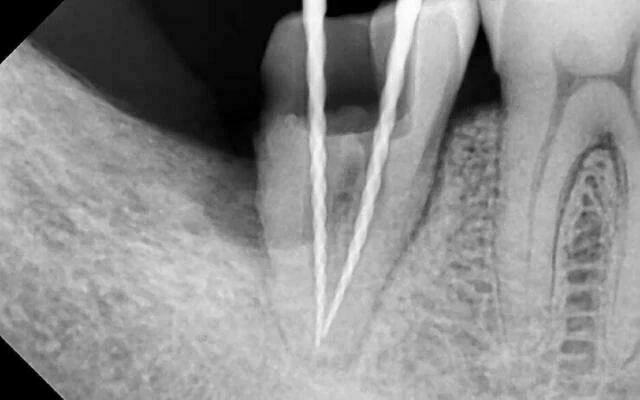

6. Hàn tủy bằng côn gutta percha F3 và cortisomol bằng phương pháp lèn ngang nguội. Kiểm tra lại độ khít sát bằng phim âm bản.

7. Ảnh trong miệng sau hàn. 2 ống gần (mũi tên xanh), 1 ống xa (mũi tên đỏ).